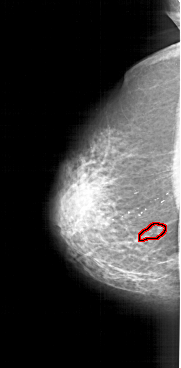

A_1123_1.LEFT_CC

LEFT_CC LINES 6256 PIXELS_PER_LINE 3076 BITS_PER_PIXEL 12 RESOLUTION 43.5 OVERLAY

FILE: A_1123_1.LEFT_CC.OVERLAY

TOTAL_ABNORMALITIES 1

ABNORMALITY 1

LESION_TYPE CALCIFICATION TYPE PLEOMORPHIC DISTRIBUTION SEGMENTAL

LESION_TYPE MASS SHAPE LOBULATED MARGINS ILL_DEFINED

ASSESSMENT 4

SUBTLETY 4

PATHOLOGY BENIGN

TOTAL_OUTLINES 1

BOUNDARY